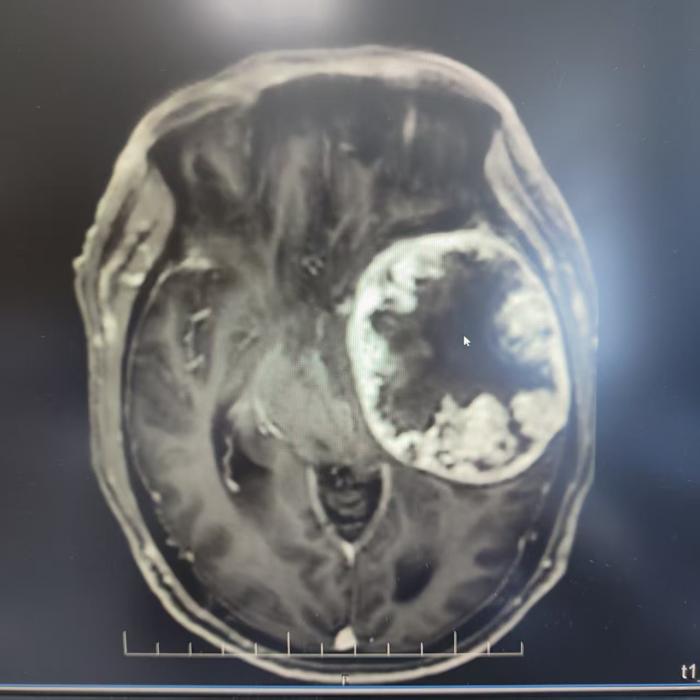

术后

术后,加速康复体系持续发力。专业护理团队密切监测患者状态,结合早期康复训练,让患者在手术当日麻醉清醒后,便能神志清晰地遵医嘱活动四肢,神经功能评估良好。得益于微创手术带来的极小创伤,患者恢复良好,头晕乏力症状显著改善。术后仅 14 天,身体状态便达到出院标准,顺利回归家庭。